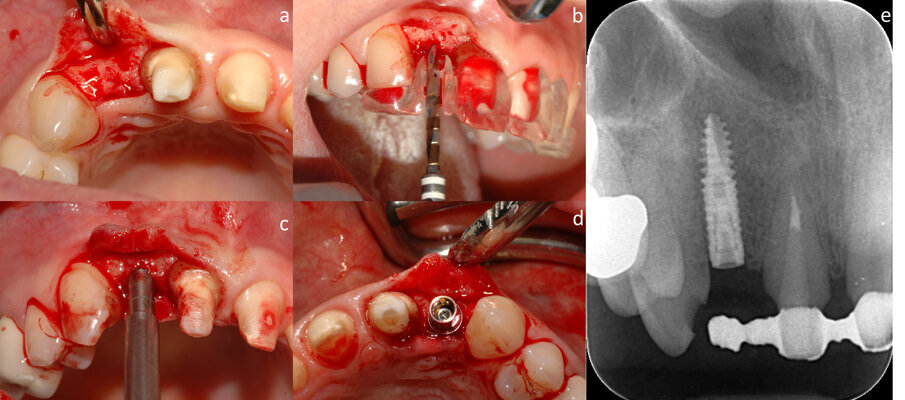

Prima della chirurgia, viene fatto fare uno sciacquo del cavo orale con una soluzione di clorexidina 0,20% per 1 min (Corsodyl, Glaxo-SmithKline). Il posizionamento implantare viene eseguito con l’aiuto di una dima, fabbricata sulla base della tomografia computerizzata cone beam (CBCT). Viene eseguita un’incisione a spessore totale in cresta, che si estende verso l’incisivo destro centrale, con conseguente sollevamento di un lembo a busta (Fig. 2a). Si procede alla preparazione del sito implantare (Figg. 2b, 2c) e al posizionamento dell’impianto (Xive, Dentsply, York, PA, USA) (Figg. 2d, 2e).

Fig. 2 - Incisione a spessore totale e sollevamento di un lembo a busta (a), inserimento dell’impianto in corrispondenza dell’elemento dentale mancante con l’aiuto di una guida chirurgica (b, c, d), aspetto radiografico dell’impianto (e).